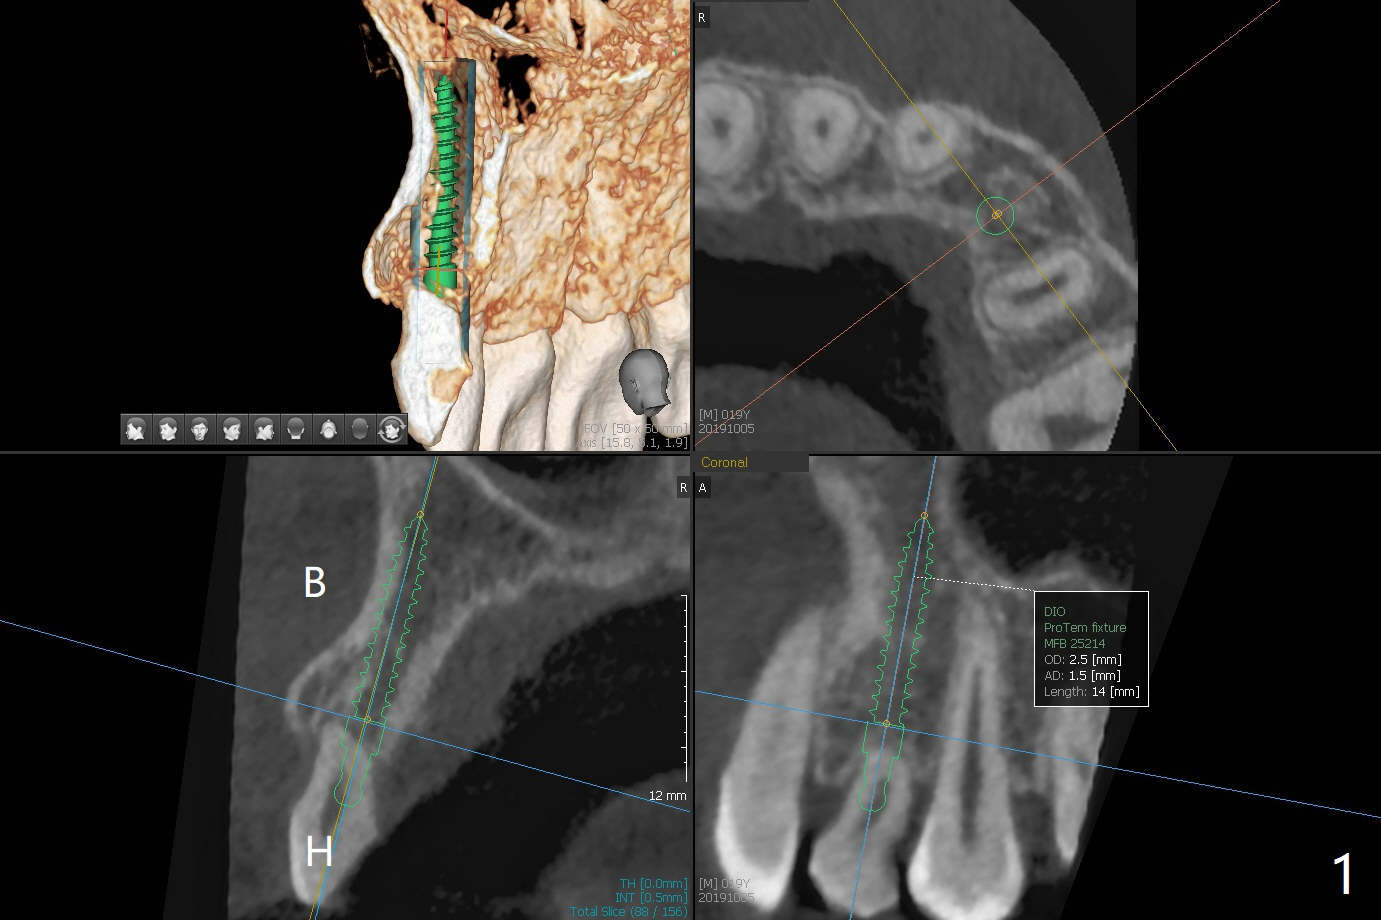

Since there is limited vertical and horizontal (buccopalatal) space at H, it appears that 1-piece implant may offer simple treatment to avoid angled abutment (Fig.1). Because of the thin concave buccal plate over the narrow implant (Fig.2,3,4 *), a remote incision will be made immediately post implantation (Fig.5 red line). After subperiosteal dissection, bone graft will be deposited to avoid implant thread exposure and restore the canine prominence (Fig.6,7). Prepare PRF for sticky bone. Take preop photo to show buccal apical concavity.